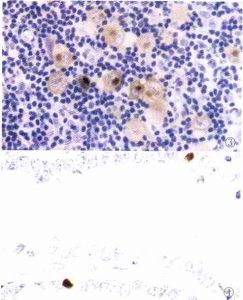

2.病理學 小腸原發性淋巴瘤絕大部分屬非霍奇金淋巴瘤,常見類型是黏膜相關組織淋巴瘤(MALT 淋巴瘤)。肉眼所見:腫塊為孤立性或多發性,多發性又可分為瀰漫性及散在性。瀰漫性者可見黏膜皺襞瀰漫增厚伴有小結節、小息肉狀突出物,常累及一段腸管;孤立性者傾向於呈環形,可致腸腔狹窄。

4.組織病理學檢查。